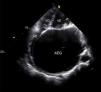

Echocardiography revealed a giant left atrium (GLA), with an anteroposterior diameter of 10.5 cm and a volume indexed to body surface area of 1054 ml/m2 (Figure 2 and Video 1); dome-shaped mitral valve, suggesting a rheumatic etiology (Video 2), with severe regurgitation and stenosis; and severe tricuspid regurgitation, with pulmonary artery systolic pressure of 74 mmHg.